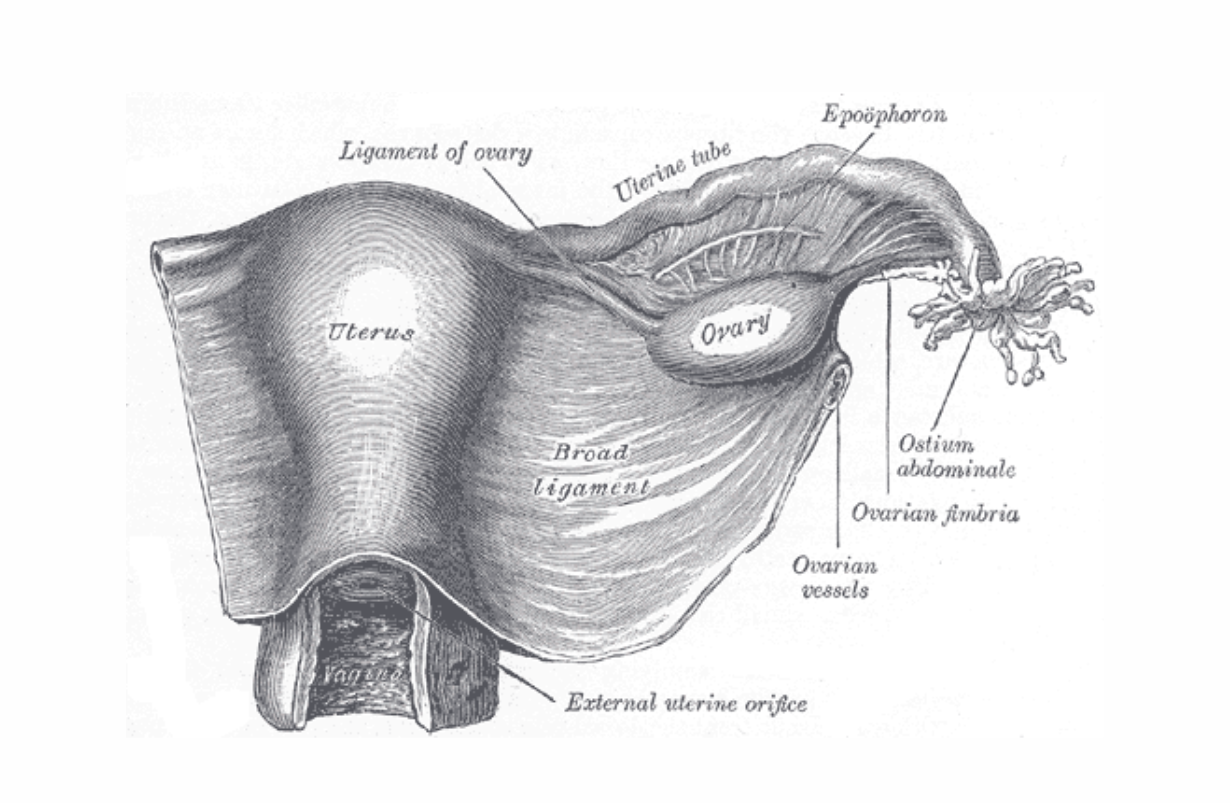

Endometriosis

Endometriosis involves the growth of uterine-like tissue within the ovaries, fallopian tubes, and elswwhere in the pelvis. It is often painful.

Pregnancy (second and third trimesters)

Usually divided into three month trimesters. These contraindications apply only in the second and third trimesters, when the placenta is larger. One of the chief worries is that twisting will separate some of the placental tissue from the uterus. BENEFICIAL POSES: Upavista Konasana, Baddha Konasana, Gomukhasana, Garudasana, Leaning. EXPLANATION: The uterus is held in place by six paired ligaments, the uterosacral, the cardinal, broad, round, ovarial, and indirectly, the ovarian suspension ligaments. Twists tighten one of each ligament pair, asymmetrically tugging the gravid uterus to one side, producing shearing forces that may dislodge some or all of the placenta. However, symmetrical poses of moderate intensity that elongate and promote control of adductors, such as Upavista Konasana and Baddha Konasana are recommended. Toward the middle of pregnancy, the placenta begins to secrete the hormone relaxin, which, as the name suggests, relaxes many ligaments, allowing the uterus to grow exponentially and the young one to exit the birth canal. At this point the mother begins to carry a good deal of weight in her abdomen, and puts significant and unfamiliar strain on the sacroiliac joints, the ligaments of which are now too flexible to resist the extra stress. Sacroiliac joint derangement is countered by the series Gomukhasana, Garudasana, and 'Leaning,' the latter pictured in the video below. REFERENCES: Jiang Q, Wu Z, Zhou L, Dunlop J, Chen P. Effects of yoga intervention during pregnancy: a review for current status.Am J Perinatol. 2015 May;32(6):503-14. doi: 10.1055/s-0034-1396701. Epub 2014 Dec 23. Martins RF, Pinto e Silva JL.Treatment of pregnancy-related lumbar and pelvic girdle pain by the yoga method: a randomized controlled study. J Altern Complement Med. 2014 Jan;20(1):24-31. doi: 10.1089/acm.2012.0715. Epub 2013 Mar 18. Fishman, LM. "Healing Yoga - Proven postures to treat twenty common ailments." W.W. Norton and Co. New York: 2014.